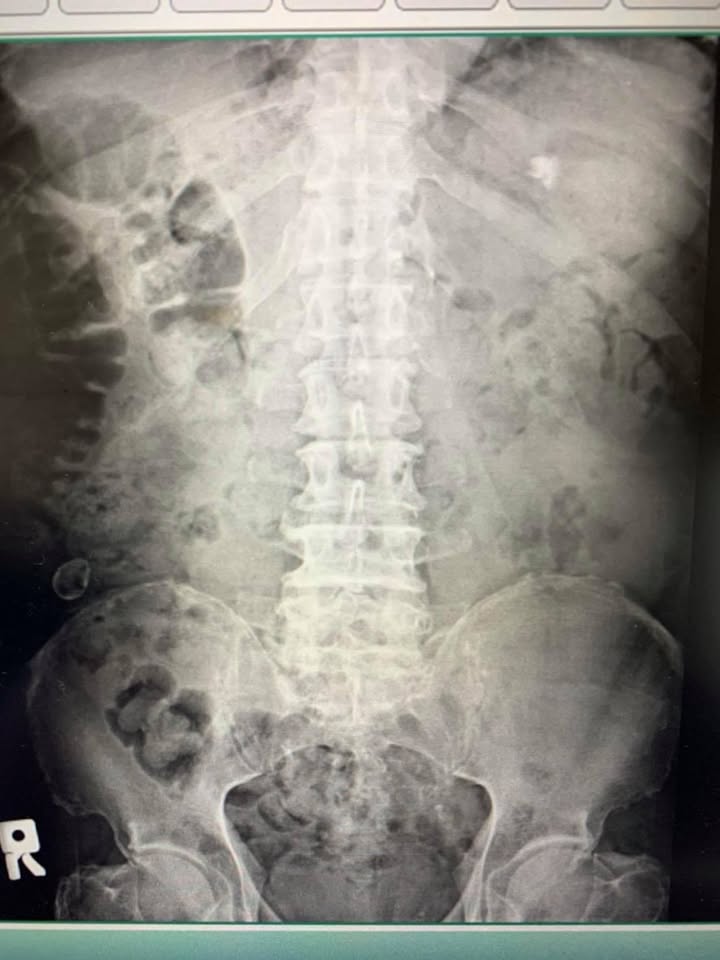

林阿伯今年摔倒後抱怨左邊腰痛連至小腿外側跟前測,疼痛的時間快四個多月,大醫院拍片檢查證實腰椎滑脫合併椎管狹窄,最近這四個月嚴重惡化!來診時候已經需要拐杖,他面露非常痛苦的表情,說大腿跟小腿被針扎的感覺非常痛苦,因為狀況其實蠻惡化的,所以按照慣例先治療四次,如果有改善就繼續治療下去,如果四次效果還是不好可能還是要去大醫院開刀

L4L5腰椎一級滑脫合併第五椎管狹窄